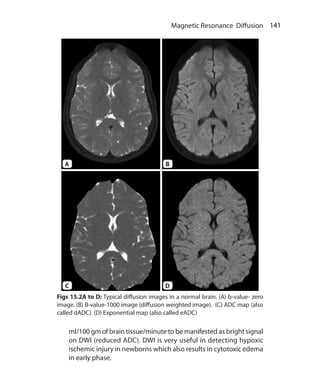

Chapter 15.  Magnetic Resonance Diffusion	 137

Clinical Applications of DWI	 140